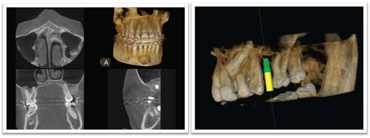

通常のレントゲンとCTとの比較

通常お撮りしていた全体像が解るレントゲンです。

お口全体の情報がかなりの確率で把握出来ます。

通常の治療の場合はこちらのレントゲンで十分です。

歯科用CT(ヨシダトロフィーパンプラス)にてアゴの骨の立体的な形態や、神経の位置把握、さらに骨密度の診査などを調べます。

パノラマと3Dセンサーを駆使した回転式デジタルレントゲン。

デジタルにより従来のフィルムを使用したレントゲン撮影に比べ、人体に受ける放射線の量を約1/4~1/10に抑える事が可能に、またCT(3D)機能により断層写真、立体的な撮影ができますので、インプラントのみならず、あらゆる歯科診療でより正確な診断と安全確実な診断が行えるようになりました。

CTによる3次元画像により、通常のレントゲン写真ではわからなかった部分が、精密・立体的に見ることができ、インプラント治療の精度も飛躍的に向上します。

歯科治療の従来の診断を大きく変えるCTスキャンの導入により今まで2次元のレベルでの診断が3次元立体画像でのレベルに変わり多くの情報を提供してくれます。